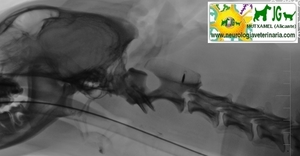

Radiografía digitalizada de cachorro de Siberian Husky con severo trauma craneal |